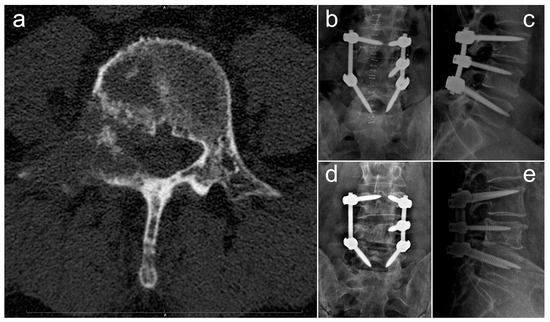

In Figure 4, we report and illustrate a case of metastasis from adenocarcinoma at the L4 level, treated using debulking and stabilization 30 months after the diagnosis of the primary tumor. After surgery, the patient received targeted chemotherapy with osimertinib and radiation therapy and lived for 30 months with a good quality of life (ambulatory status: autonomous, Frankel score E, Karnofsky score 80 at last follow-up).

Figure 4.

Radiographic images concerning a case of an L4 metastatic lesion from adenocarcinoma, treated via debulking and stabilization. (a) Preoperative axial CT scan showing the osteolytic lesion in L4; (b,c) postoperative anteroposterior (b) and laterolateral (c) Rx projections showing L3–L5 stabilization; (d,e) anteroposterior (d) and laterolateral (e) Rx projections at 18-month follow-up.